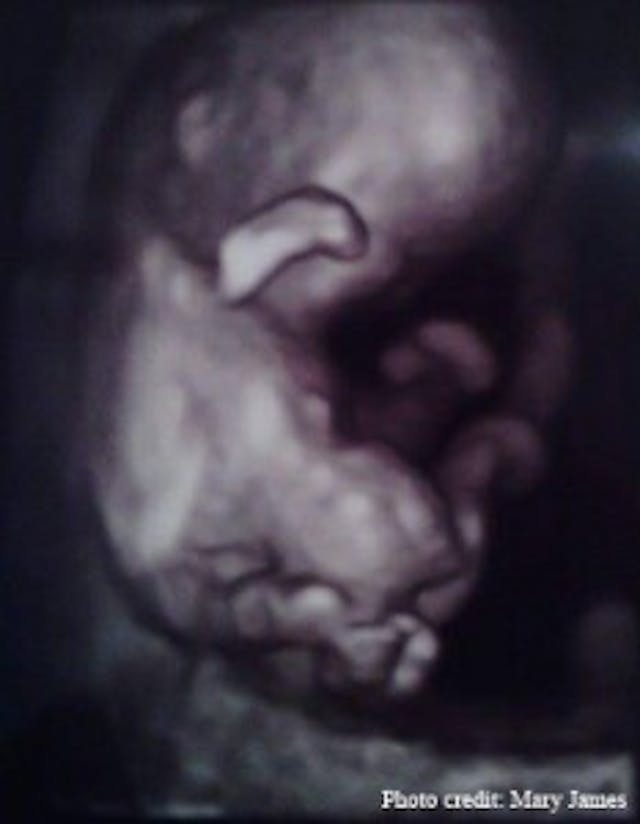

Sean and I went to the appointment together. Much to my relief, the ultrasound technician confirmed that there was indeed a live baby and I was farther along than I thought, 10 weeks already! My eyes were glued to the ultrasound screen. My baby looked like a tiny person, not just a blob. We saw it move around, waving its arms up and down just like an infant would. Facial features were even distinguishable which amazed me!

The ultrasound tech mentioned she was having trouble seeing the baby’s lower limbs, which she blamed on his position. They sent me across the hall to a specialist. This technician also couldn’t see much of the legs. I asked her if that was terribly unusual, and she tactfully indicated it was, and said the specialist would be in shortly.